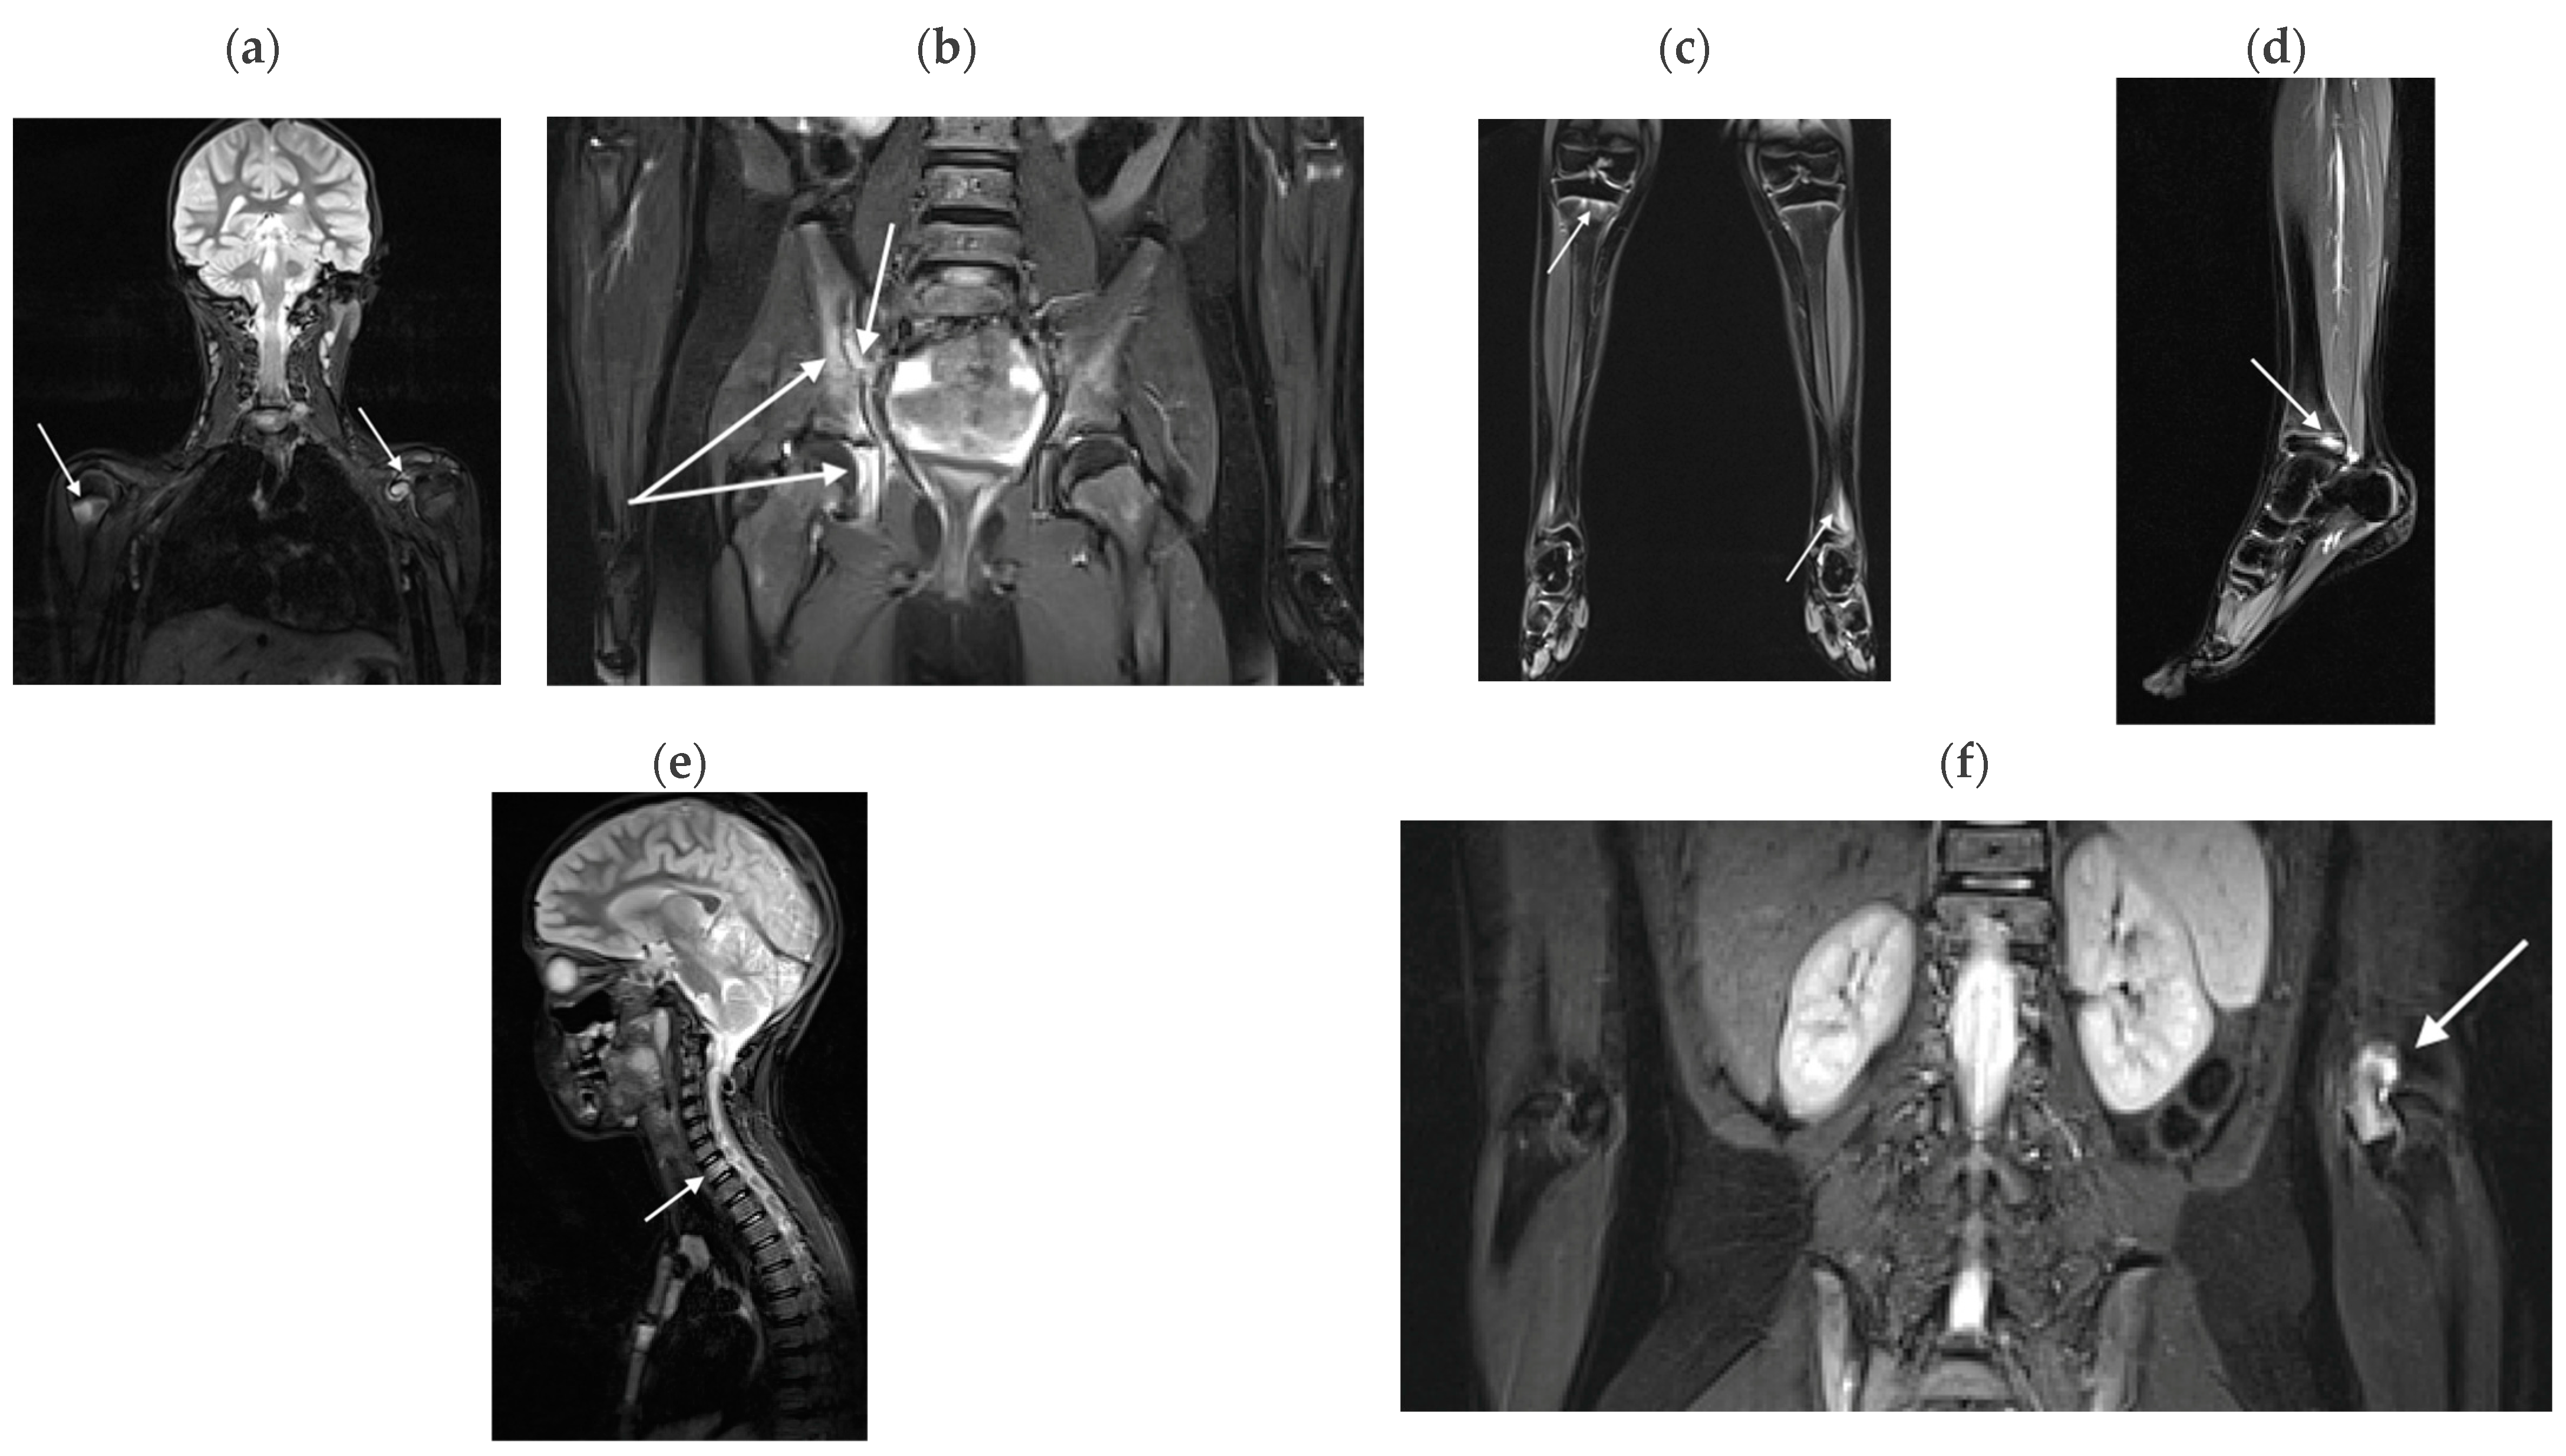

3.2.1. Bone Marrow Edema Lesions

3.2.3. Myositis

3.2.4. Enthesitis